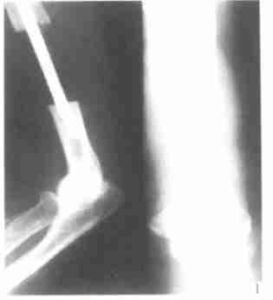

.滑膜肉瘤是發生頻率較高的一種軟組織肉瘤,好發於15-40歲,四肢的大關節附近,特別是膝關節附近好發,另外與關節無關的部位如頭頸部、腹壁、後腹膜也可發生。本病的基本X線表現有三點:軟組織腫塊,局部骨皮質破壞,腫瘤的鈣化和骨化。此病好發於關節附近,呈分葉結節狀,密度增高,邊界清楚的軟組織腫塊。其內可見骨化影,呈條狀或塊狀輪廓清楚的高密度影,部分骨化影中可見骨小梁結構,少數病例為骨化性腫塊。應與骨旁骨肉瘤、骨化性肌炎、骨肉瘤等鑑別。滑膜肉瘤是惡性程度較高的軟組織惡性腫瘤,源於關節、滑膜及腱鞘滑膜組織。發病部位以四肢的大關節為多,也可發生於前臂、大腿,腰背部的肌膜和筋膜上。主要以手術治療為主。

3.X線攝片可見軟組織腫塊,腫瘤內有不規則鈣化,骨質可有破壞,骨膜反應少。

1.X線表現約30%的病變中可以見到模糊散在的鈣化,有時可見骨膜反應,甚至侵蝕骨或侵入骨內。開始僅表現為軟組織腫塊,以後腫塊內可出現鈣化。對於病變內有點狀鈣化者應考慮與軟骨瘤或血管瘤相鑑別。2.骨掃描在掃描的晚期,可見病變內礦化活躍區的周圍有局限的攝取量增加(圖5)。由於病變的新生血管豐富,在掃描的早期可見病變區攝取量高於鄰近軟組織。